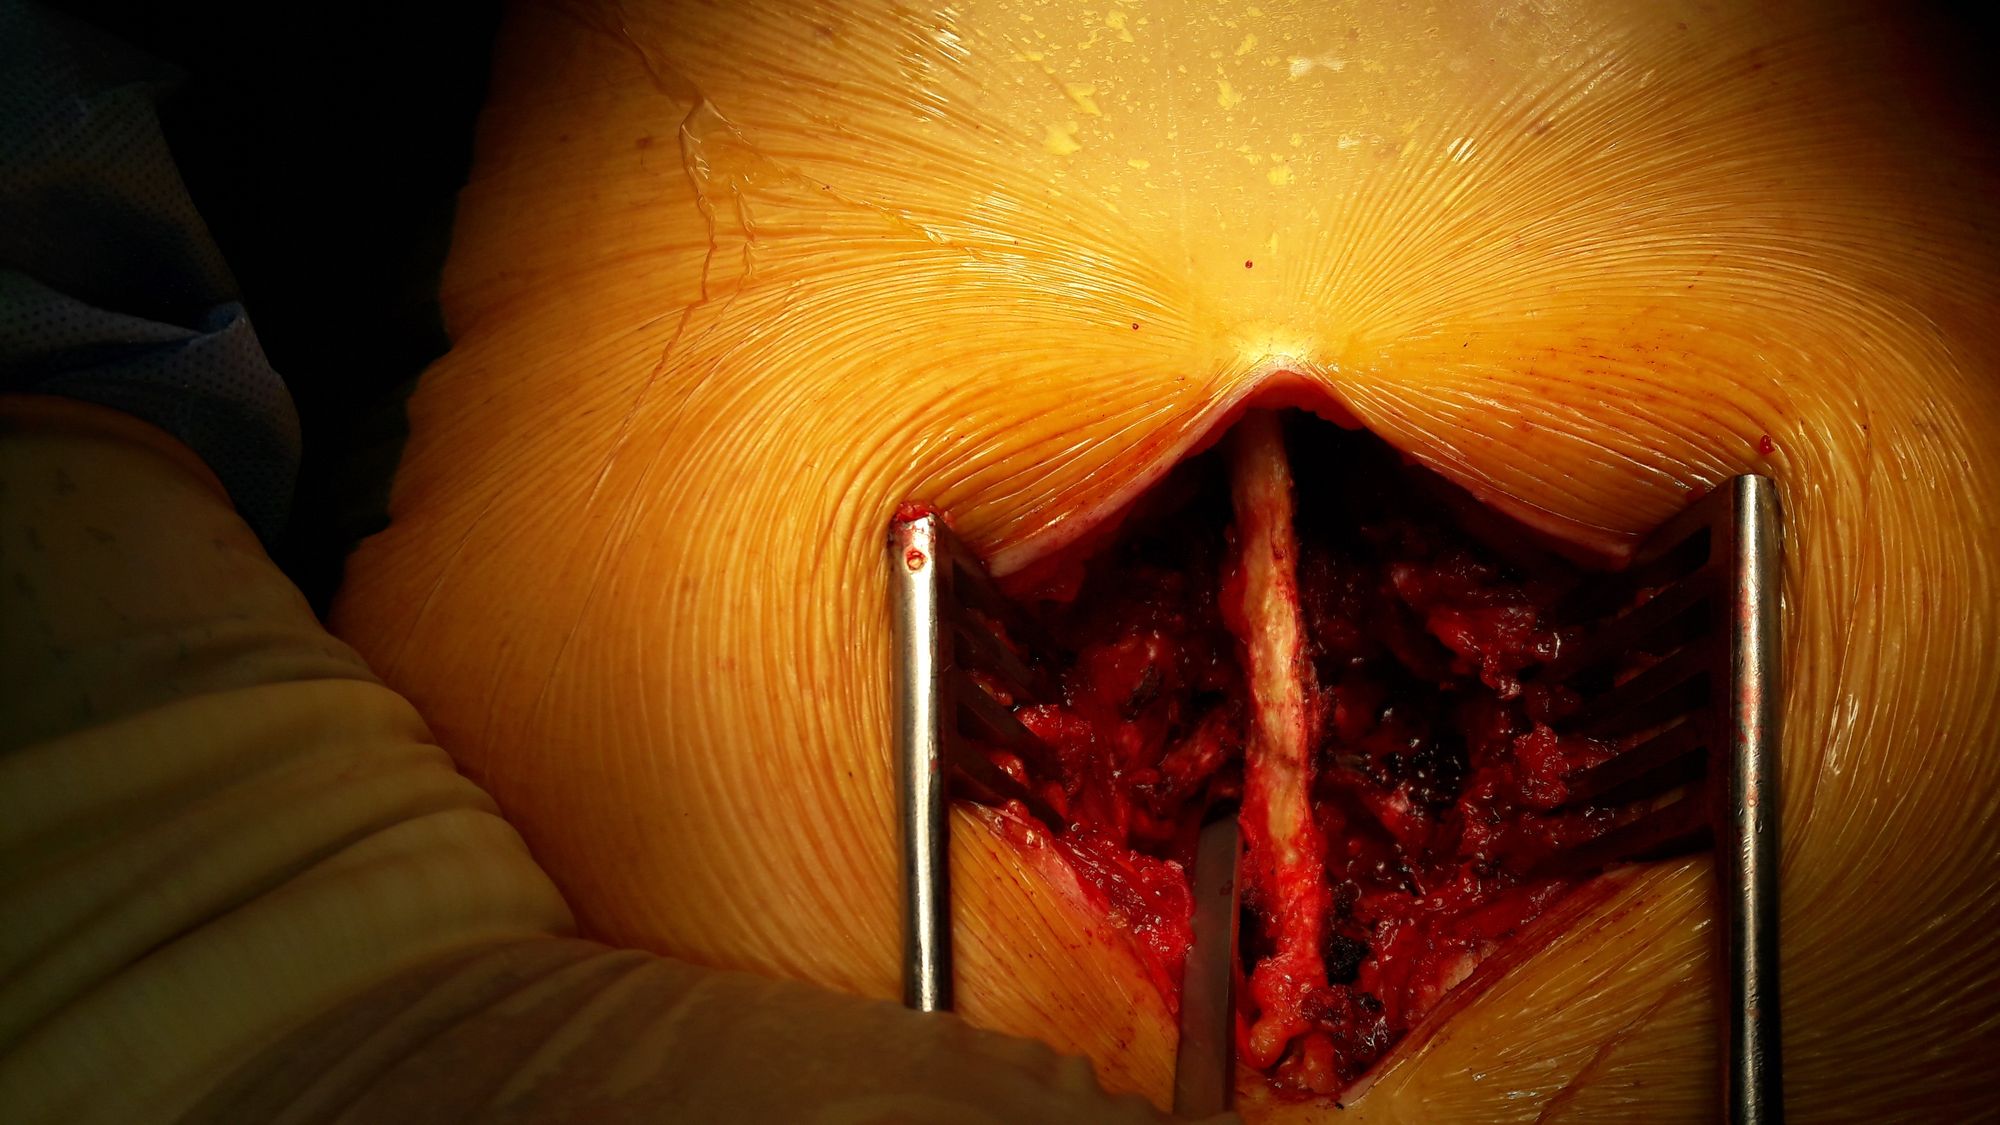

The patient is placed in prone position on a Hall frame. A medial sagittal incision is made over the spinous processes at the level of the spinal stenosis. The erector spinae muscles are detached from both sides of the spinous processes and laminae, down to the facet joints laterally which are disengaged (Fig. 2).